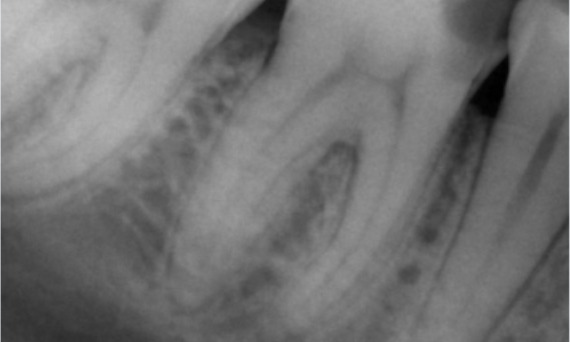

Antes: Radiolucencia periapical asociada principalmente con la raíz distal y pérdida de la lámina dura en la raíz mesial.